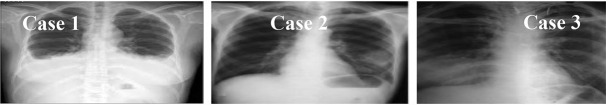

隐孢子虫是艾滋病毒阳性患者持续无法治疗的腹泻的一个重要原因,特别是在发展中国家;然而,肠外病例很少有文献记载。在此,我们报告了伊朗德黑兰伊玛目霍梅尼医院HIV患者的三例肺隐孢子虫病。尽管采用抗逆转录病毒疗法、阿奇霉素和帕罗霉素联合治疗,但所有3例患者均因严重并发症而死亡。这些病例突出了CD4计数低的HIV患者呼吸道隐孢子虫病的早期诊断和管理的重要性。

Cryptosporidium species are a significant cause of persistent untreatable diarrhea in HIV-positive patients, especially in developing countries; however, extra-intestinal instances are rarely documented. Herein, we present three cases of pulmonary cryptosporidiosis in HIV patients at Imam Khomeini Hospital, Tehran, Iran. Despite the combination treatment with antiretroviral therapy, azithromycin, and paromomycin, the death of all 3 patients occurred due to severe complications. These cases highlight the importance of early diagnosis and management of respiratory cryptosporidiosis in HIV patients with low CD4 counts.